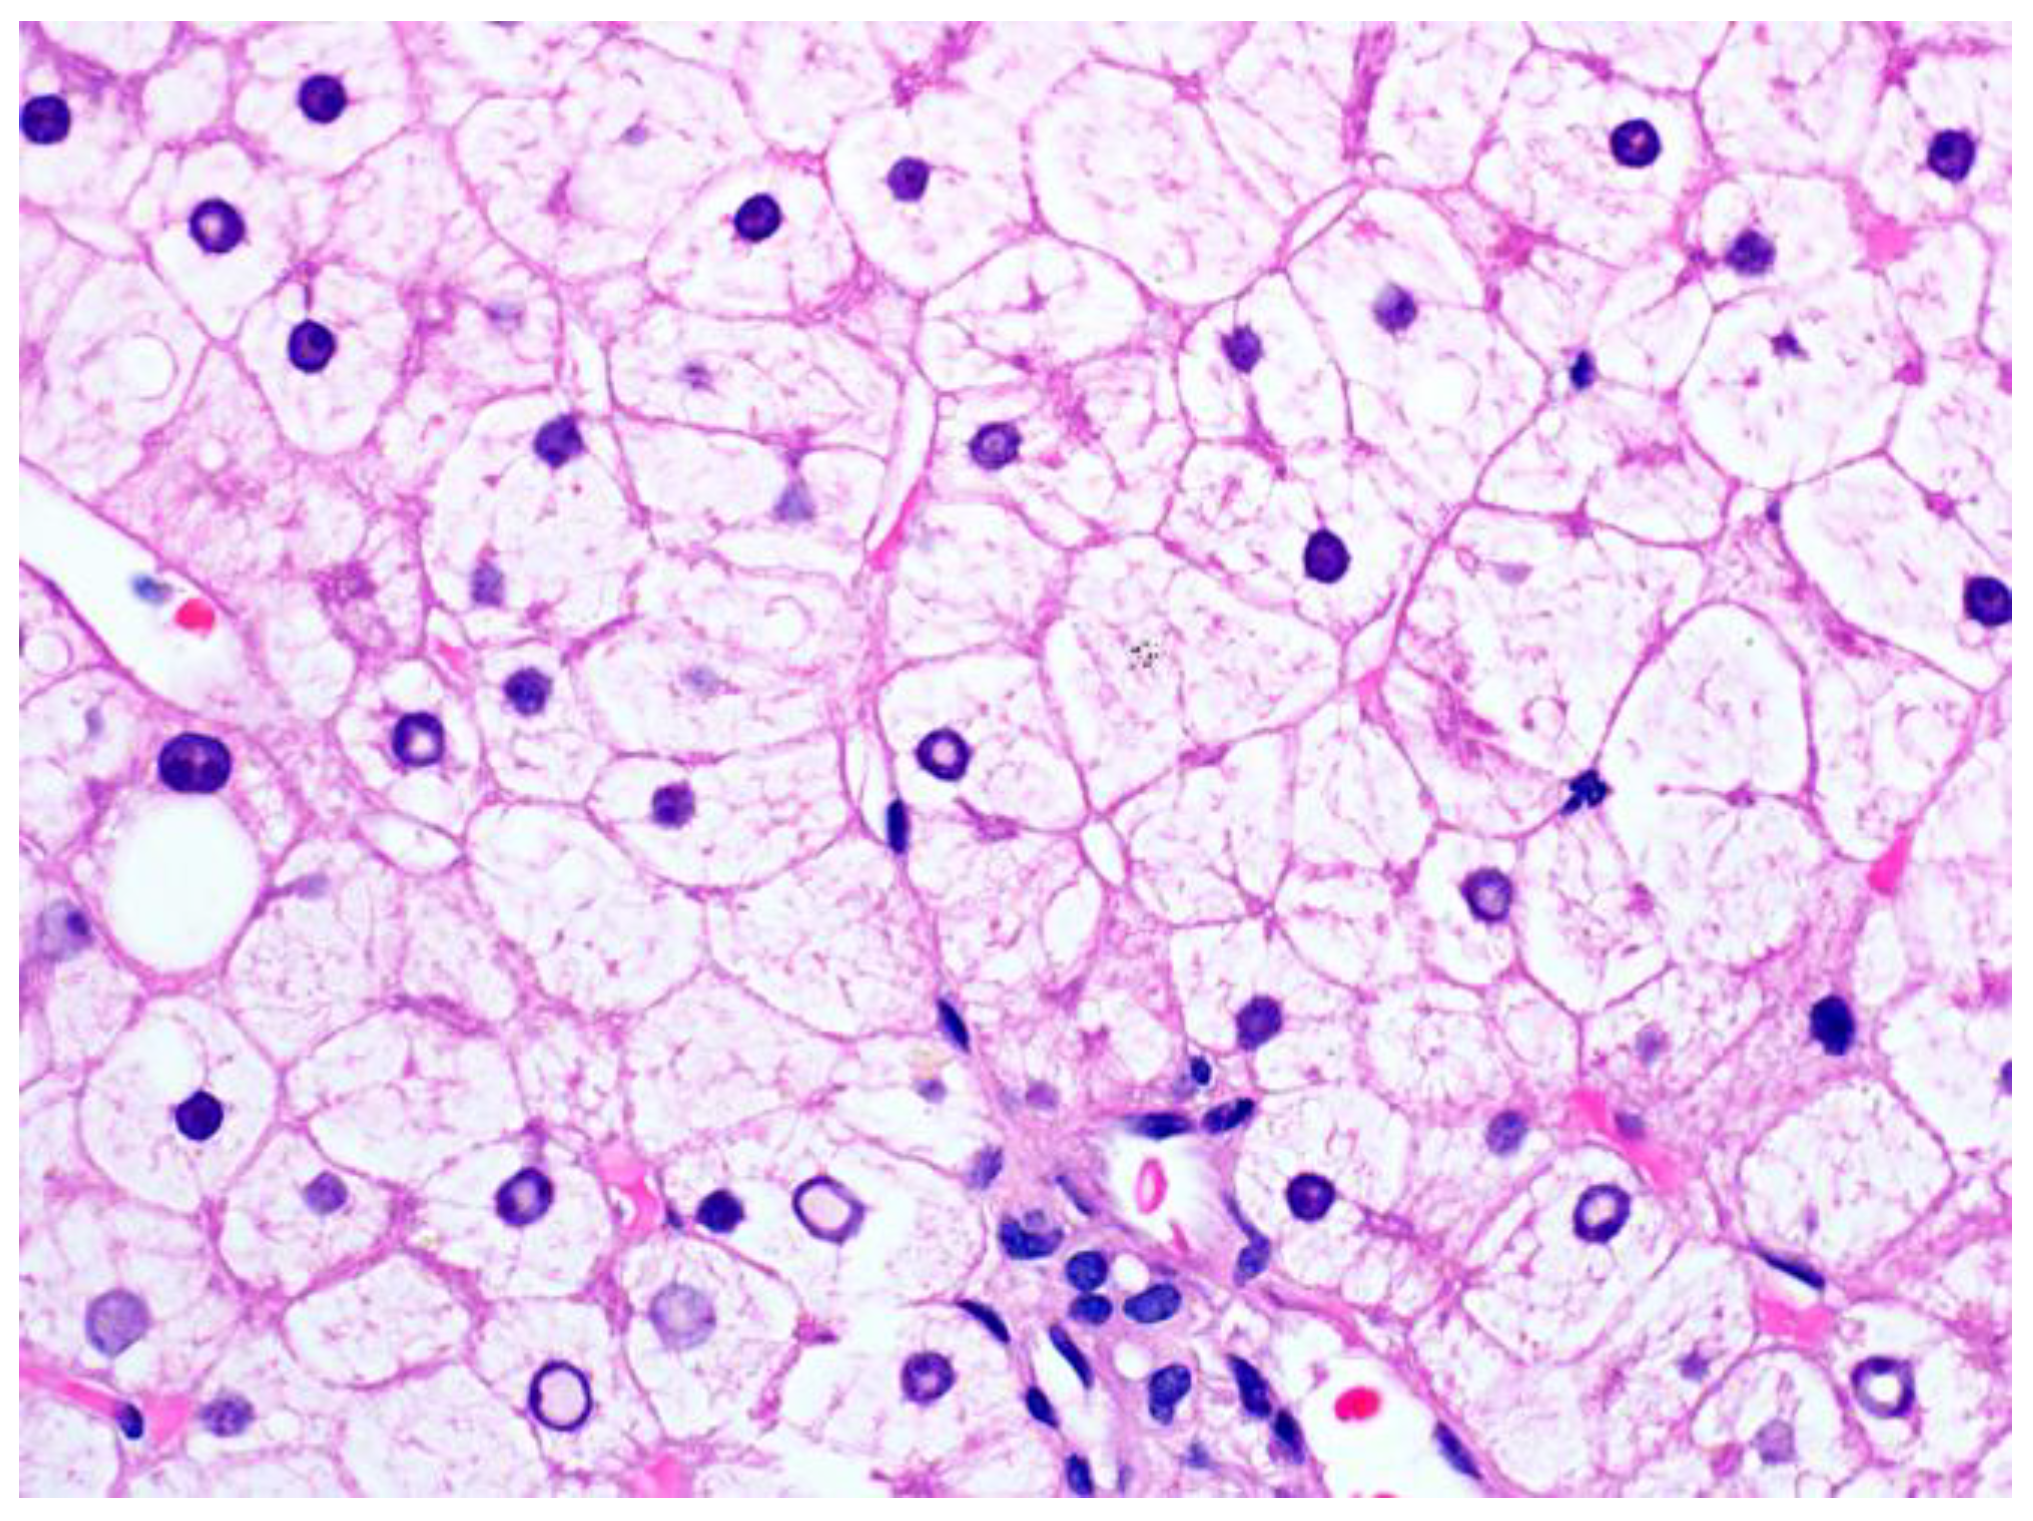

3.1.2. Pathological Findings